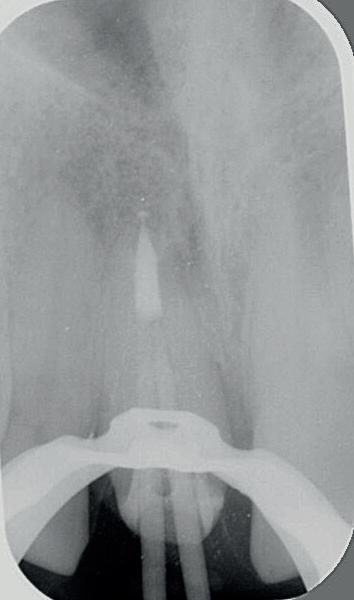

2: Röntgenfoto van 11 met zilverstift sectie

3: Pocket palatinaal 11